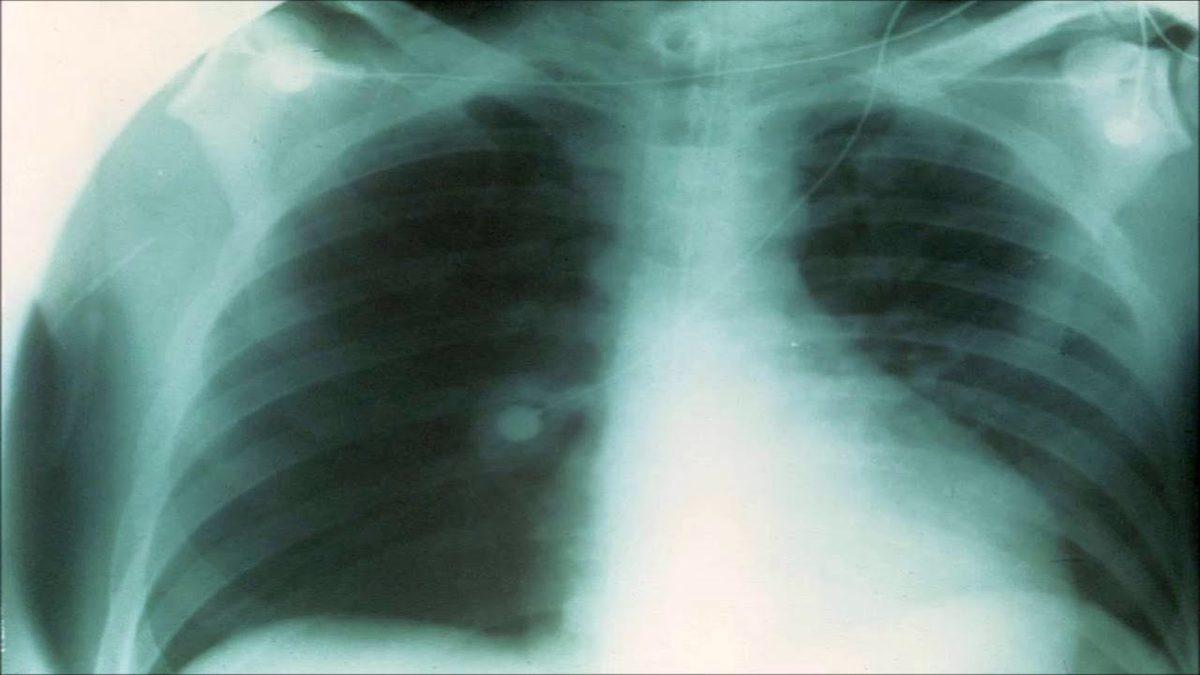

Bugün eğitimsiz olan herhangi bir insana göğüs röntgeni verirseniz size pnömanileri, nodülleri, atelaktazileri gösteremez. Hatta çoğu kişi için bu sözcükler ancak Google’dan aranıp bulunabilecek karışık kavramlardır.

Öte yandan bu ücretsiz internet sitesindeki yapay zeka, yüklenen görselleri yüzde 80 isabet oranıyla yorumluyor. Bir başka ifadeyle ortalama bir radyolog ile aynı başarı yüzdesine sahip.

Chester AI radyoloji asistanı adlı yapay zeka, Montreal Üniversitesi’nden Joseph Paul Cohen tarafından geliştirildi. Yapay zeka görseli tarayarak gerekli sonuçlara ulaşıyor. Her ne kadar Cohen bir tıp doktoru olmasa da sağlık ve derin öğrenme üzerinde çalışıyor. Daha önce BlindTool adlı bir uygulama yazan Cohen, bu uygulamayla görme engelli kişiler için telefon kamerasının kullanılabildiği bir uygulama geliştirmişti.